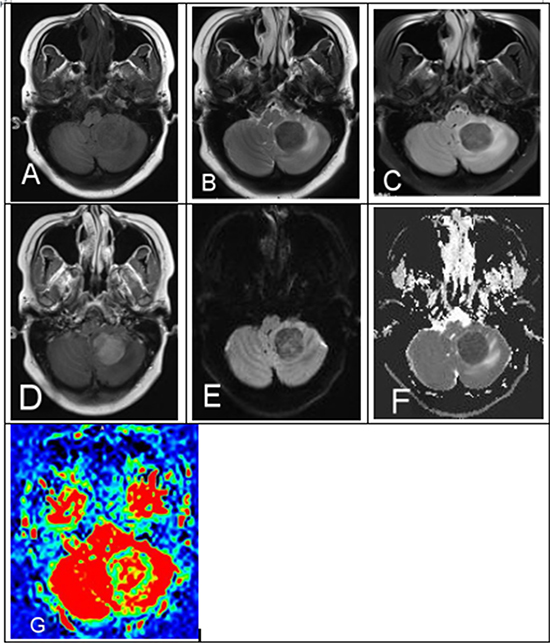

Figure 2: A 29-year-old female with a history of AML in remission presents with headaches, nausea and vomiting. (A) MRI demonstrated left cerebellum mass unenhanced T1WI, (B) T2WI, (C) FLAIR isointense-to-mild hypointense and (D) CE-T1WI showed homogenous hyperintensity. (E) DWI and (F) ADC map demonstrated mild-to-moderate restricted diffusion. (G) ASL showed mild hypointensity with mild surrounding vasogenic edema and mass effect.